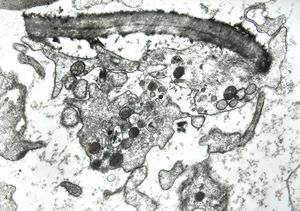

F,43y. | blood - leukemia - bacteriaemia - phagocytosed microbes

phagocytosed microbes

M,2w. | bacteriaemia - phagocytosed microbes

phagocytosed microbe